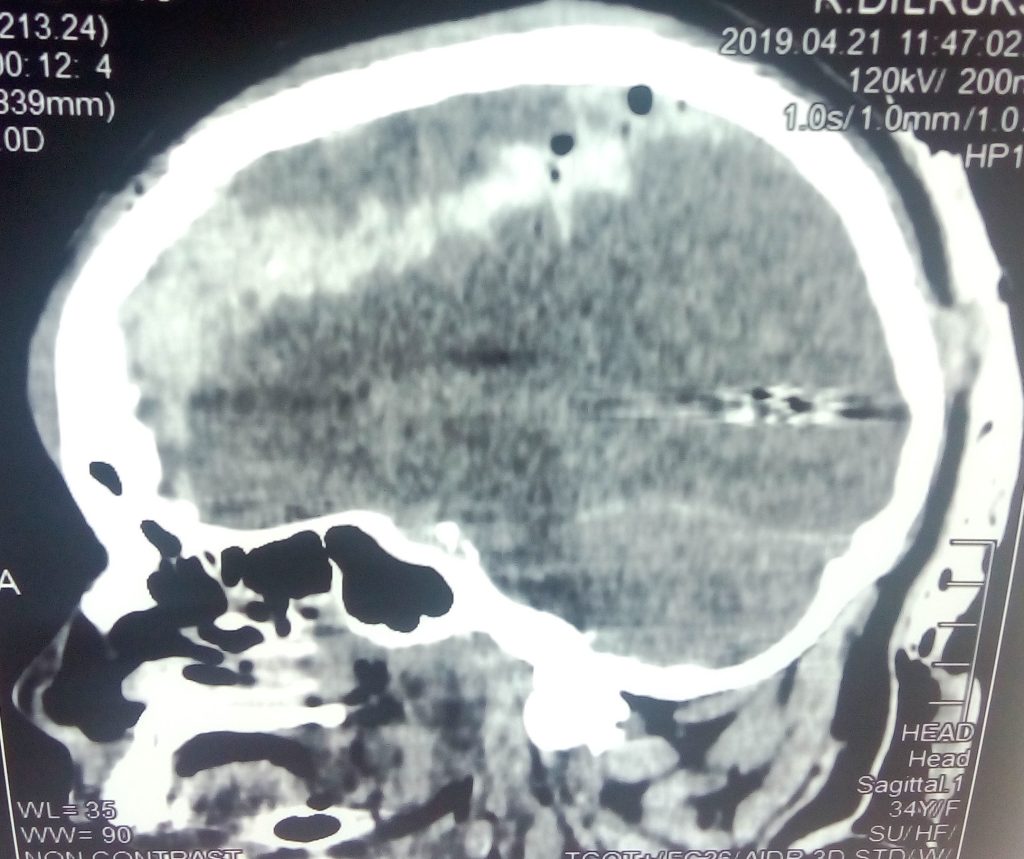

3.Tertiary-Results from individuals being thrown by the blast wind. Any body part may be affected. Types of Injuries-Fracture and traumatic amputation, Closed and open brain injury